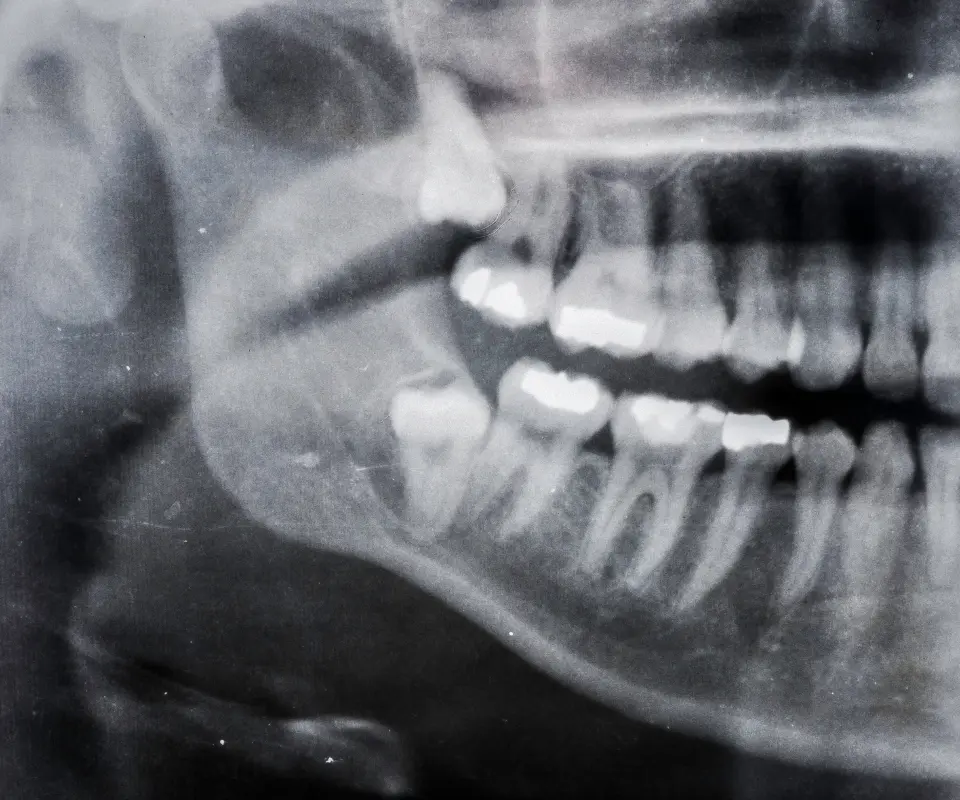

Quick Exam & X-ray

We assess your teeth to confirm if wisdom teeth surgery is needed.